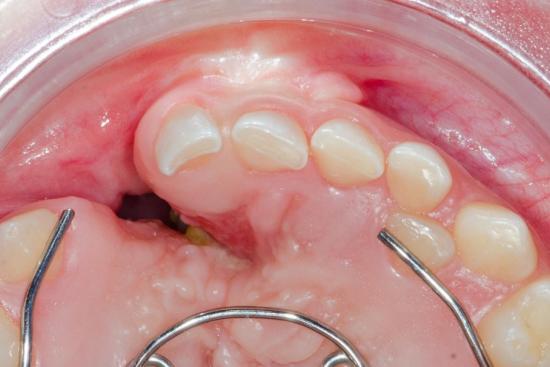

فتح اللثة:

يعمل الطبيب المعالج على زراعة عظام اللثة من خلال إجراء شق جراحي بها للكشف عن العظام، وتنظيف المنطقة المصابة، وإزالة أي أنسجة غير صحية.